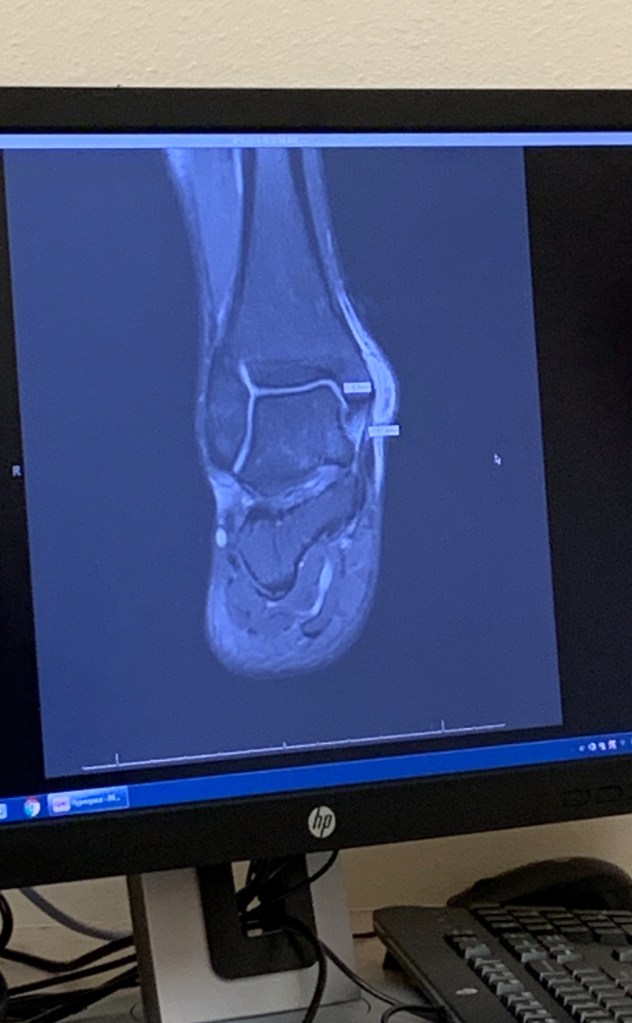

오른쪽 발목 수술을 받게 됐고그때만 해도 다시 얼음 위에 설 수 있을지, 스케이트를 계속 탈 수 있을지 정말 막막했거든. 회복 기간 동안 아이도 많이 지쳐 있었고 엄마인 나도 무기력한 날들이 많았어. 그래도 포기하지 않고 묵묵히 재활에 집중하는 아이 보면서 속으로 몇 번이나 울컥했던 기억이 나. 병원 다니고, 재활 훈련하고, 조금씩 다시 얼음 위에 서기까지 정말 많은 시간과 기도가 필요했어.